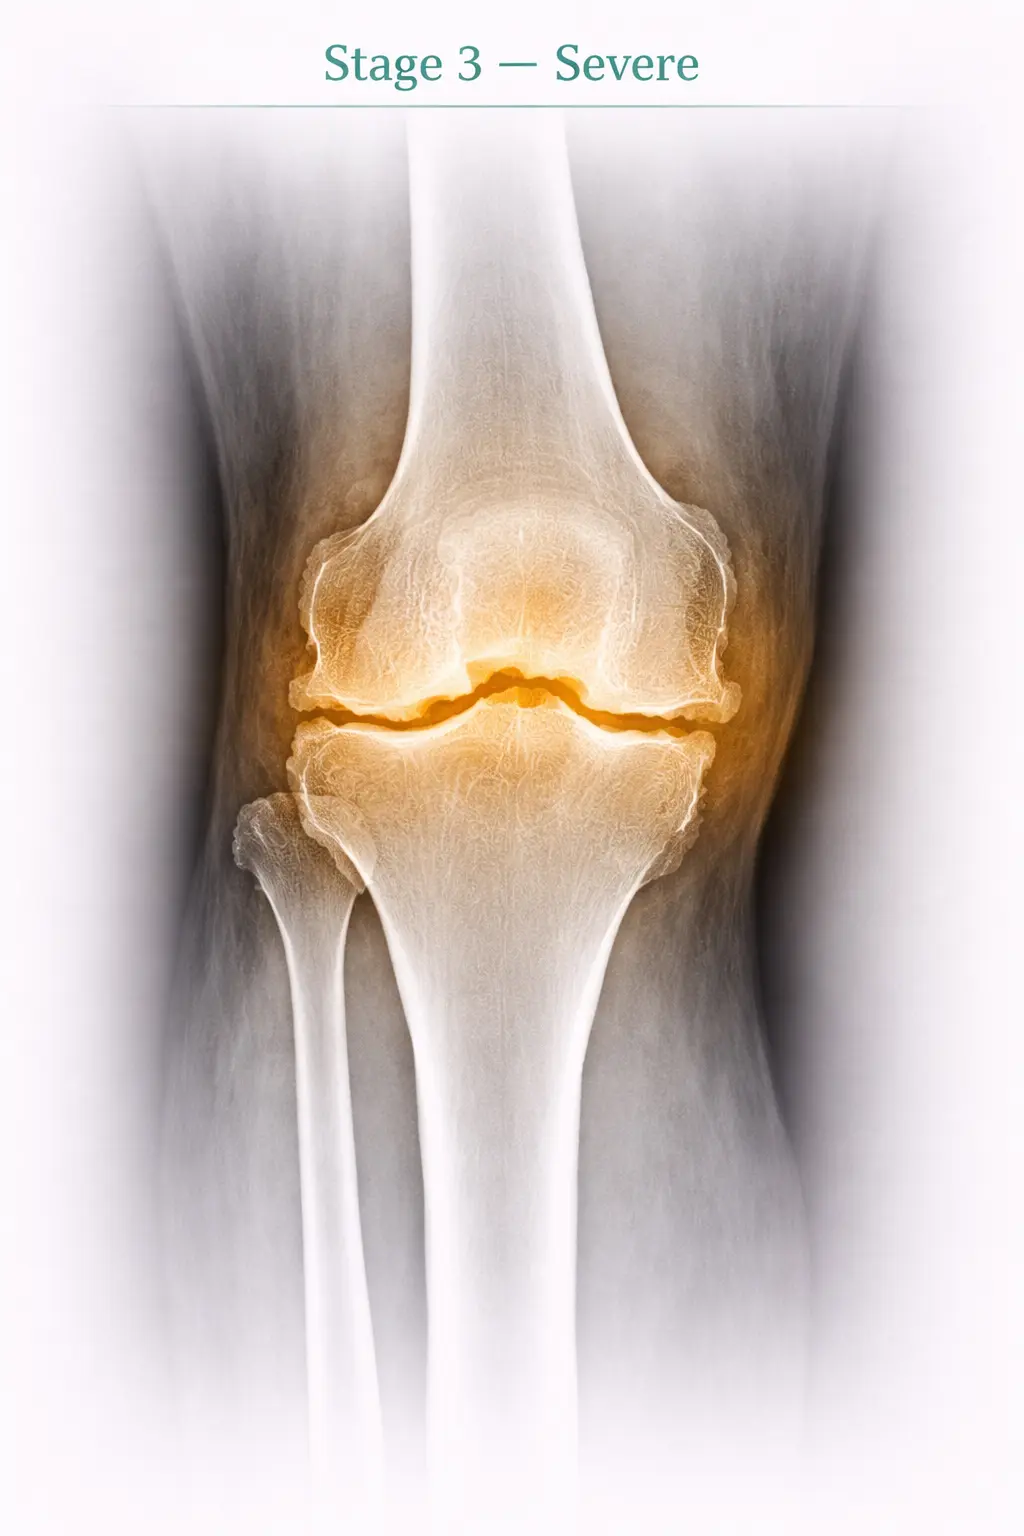

3

Stage 3

Severe

Symptoms

• Difficulty in stair up-down

• Limp while walking

X-ray Findings

• Gross reduction in joint space

• Bone spur (osteophyte formation)

Stage 3 - Severe osteoarthritis in knee joint X-ray